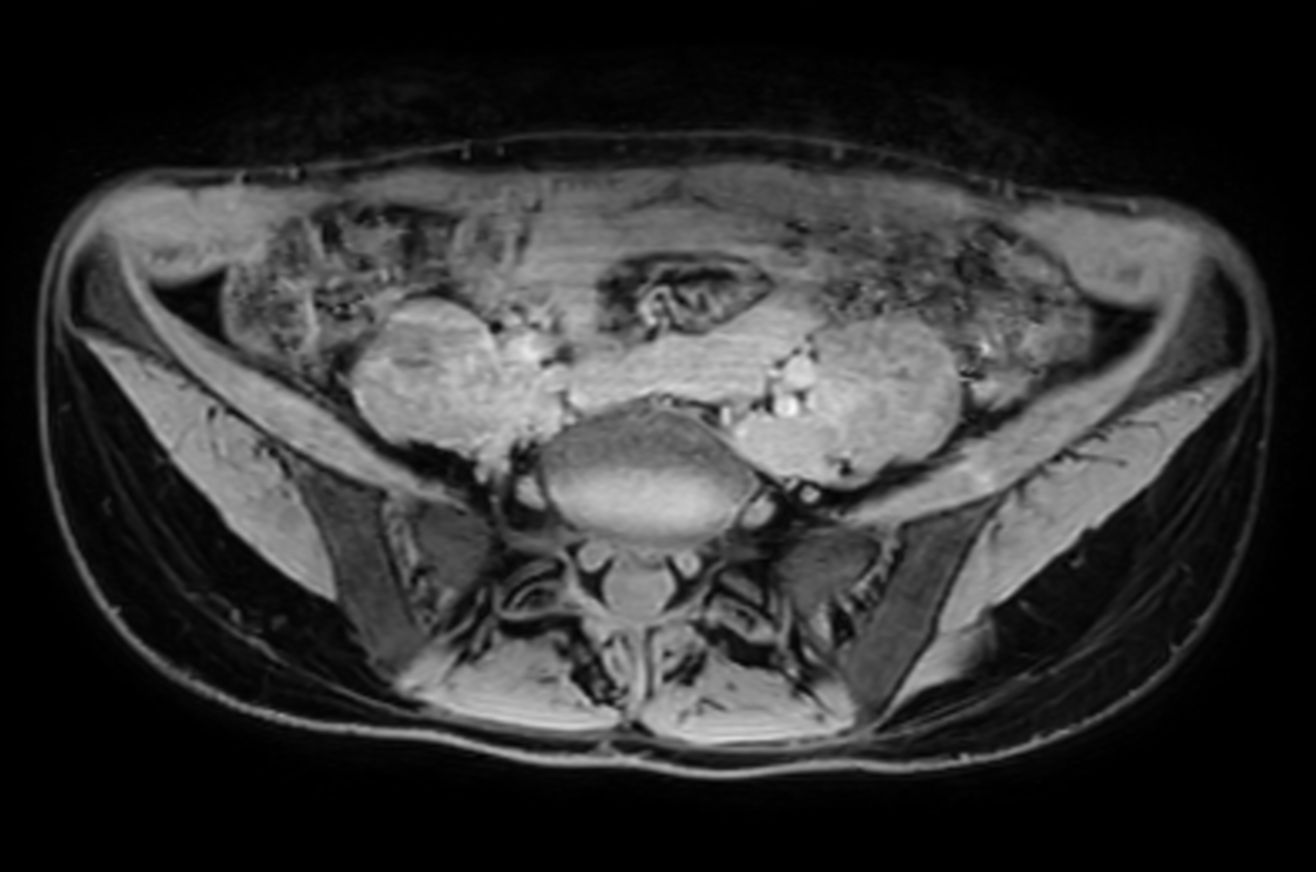

Lumbar Plexus imaging